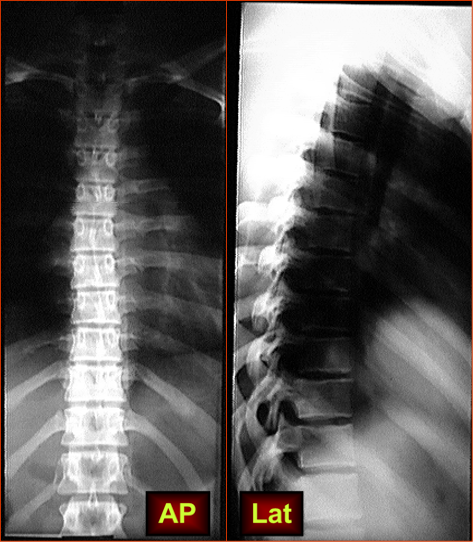

Thoracic Vertebrae

(a) Frontal view.